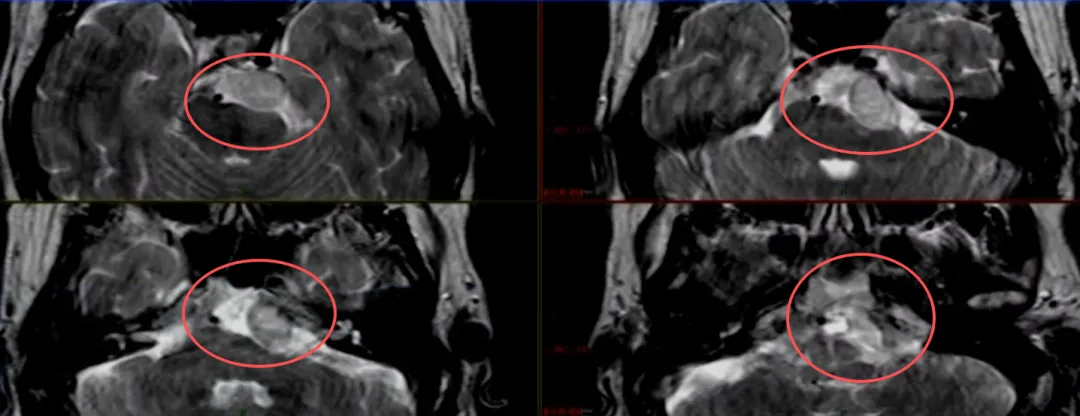

本例手术采用岩前入路,通过前岩骨解剖结构吸除肿瘤,因肿瘤位置较低(低于内听道水平)。

手术重点关注两个方面:降低脑脊液漏风险和保护外展神经(CNVI)。福教授将内镜作为手术第二部分,用于切除肿瘤下部和区分外展神经。患者围手术期出现外展神经功能暂时性受损,但很快恢复,后续能继续从事司机职业——这也是福教授治疗该患者的首要目标。此外,该患者未出现脑脊液漏并发症。